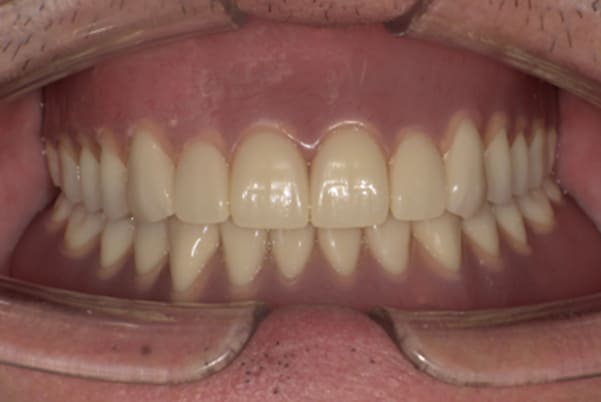

奥歯がなくなり、放置されたことで、かみ合わせが深く乱れた状態でした。

乱れたかみ合わせを治し、治療途中で見た目は患者様がご納得いく、歯の大きさ、色、形をご一緒に確認しながら入れ歯を最終的に作製しました。

-

上顎治療後

下顎治療後